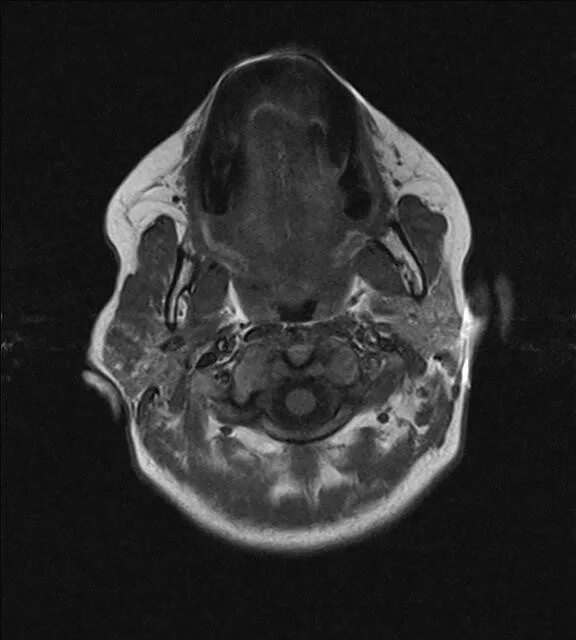

Кт тканей